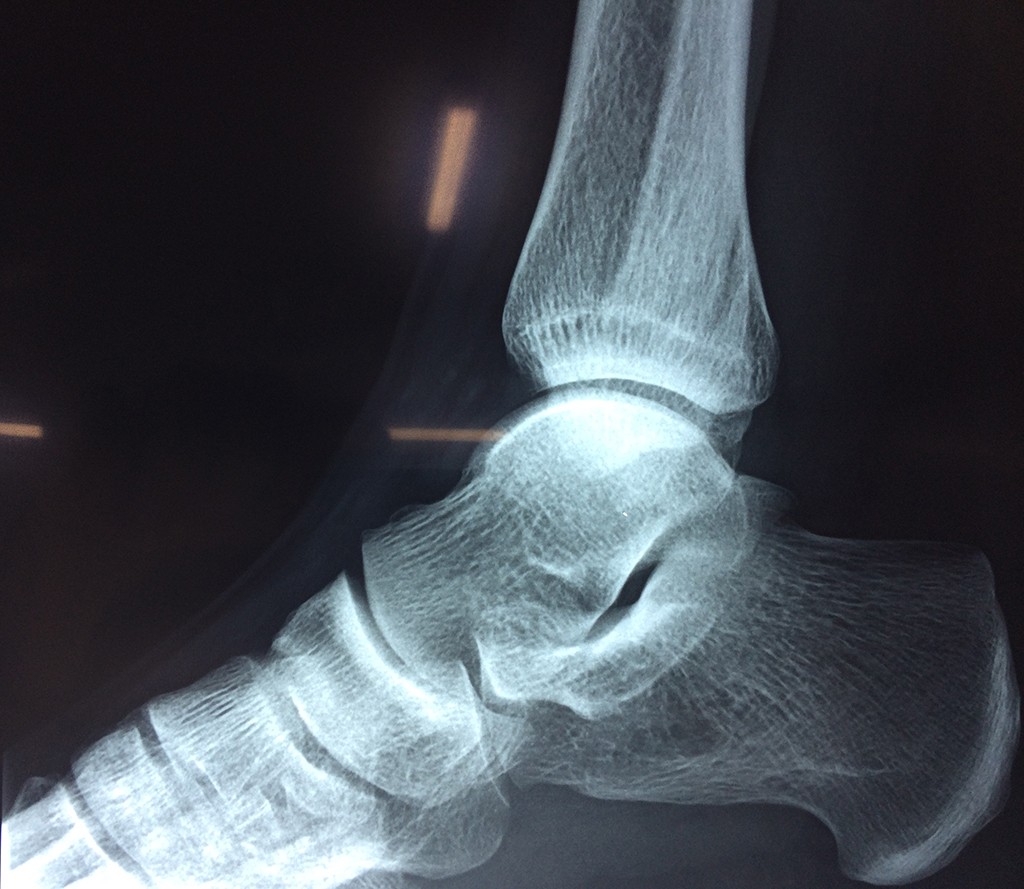

Una fractura de tobillo es la rotura de uno o más de los huesos del tobillo. Estas fracturas pueden ser:

- Parciales (el hueso está sólo parcialmente fisurado, no del todo).

- Completas (el hueso está perforado y está en 2 partes).

- Producirse en uno o ambos lados del tobillo.

Algunas fracturas de tobillo pueden requerir cirugía si:

- Los extremos de los huesos están desalineados entre sí (desplazados).

- La fractura se extiende hasta la articulación del tobillo (fractura intra-articular).

- Los tendones o ligamentos (tejidos que sujetan los músculos y los huesos entre sí) están rotos.

- El médico cree que sus huesos probablemente no sanen apropiadamente sin cirugía.

- El médico considera que la cirugía puede permitirle una recuperación más rápida y confiable.

- En los niños, la fractura involucra la parte del hueso del tobillo donde el hueso está creciendo.